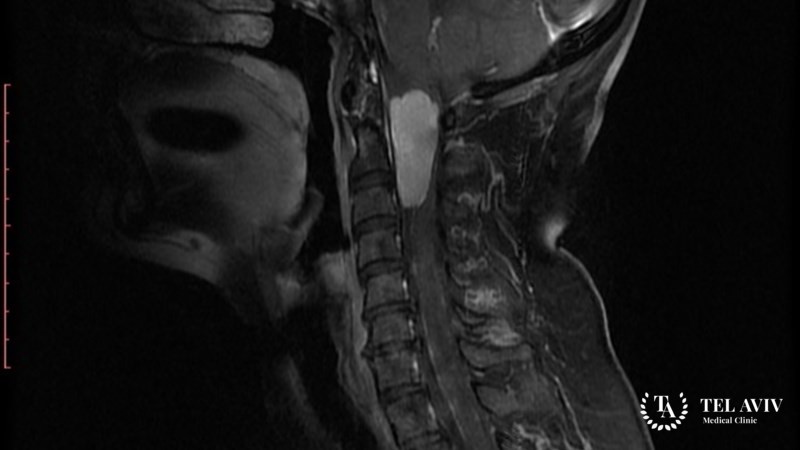

- МРТ или КТ;

В ведущей израильской клинике работает настоящая команда профессионалов, которая более 10 лет занимается выявлением и лечением различных патологий, в том числе менингиомы спинного мозга и позвоночника. Наше отделение оснащено современной аппаратурой, которая помогает использовать инновационные технологии терапии. Наш медперсонал ежегодно повышает свои навыки в ведущих европейских и американских заведениях. Мы стараемся создать максимально комфортные условия пребывания на всех этапах терапии.